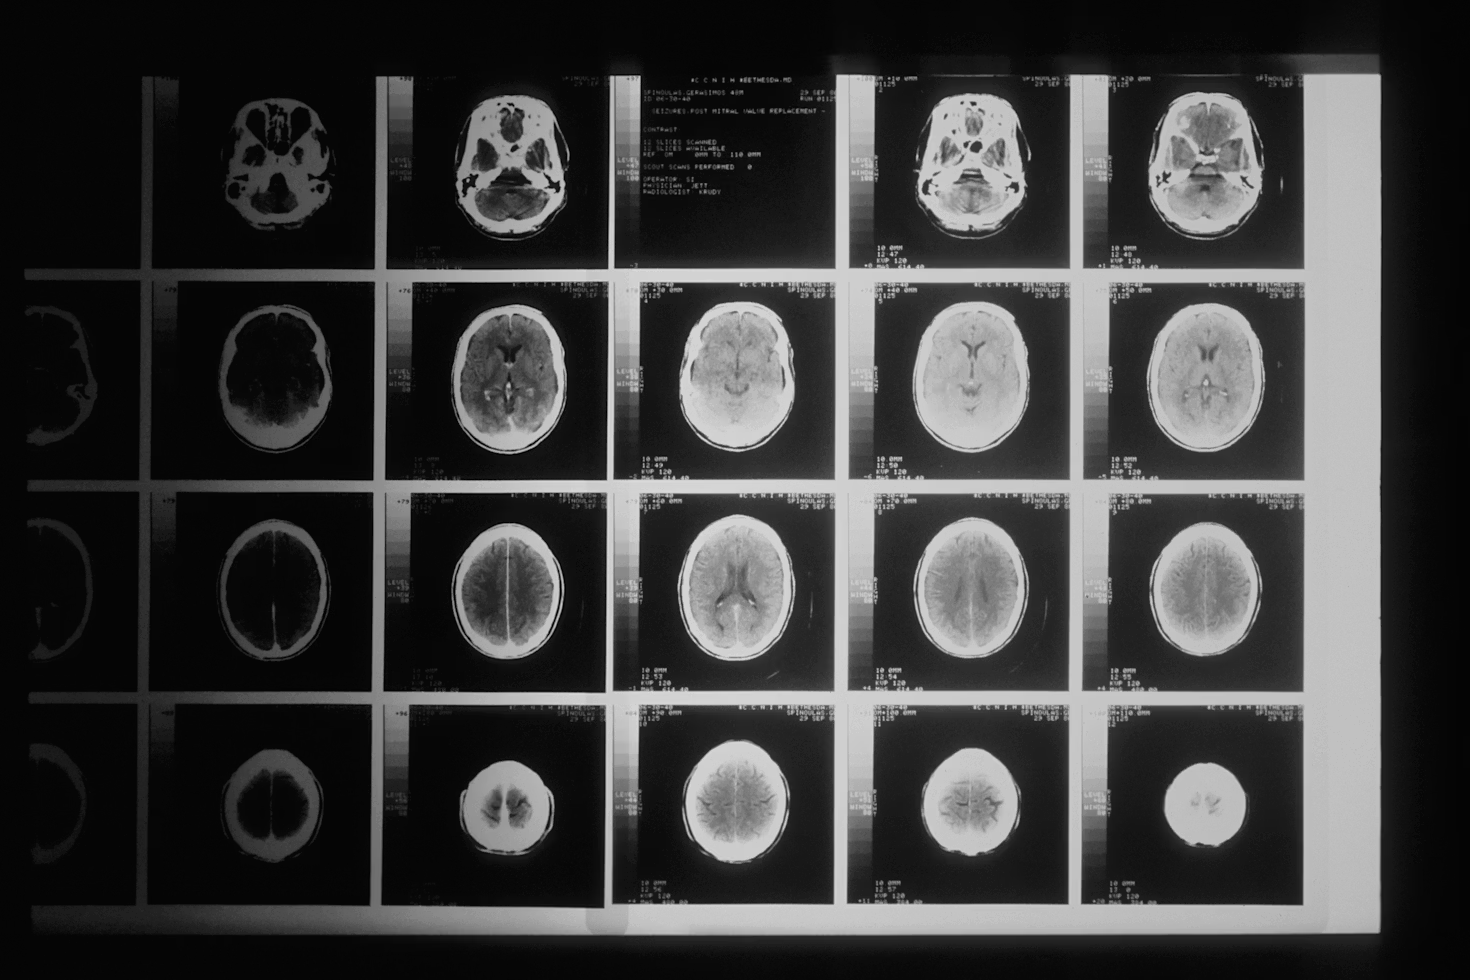

What Gadolinium Contrast Does During an MRI

Gadolinium-based contrast agents work by altering the magnetic properties of nearby water molecules, creating brighter or darker areas in the resulting images. This enhancement is particularly valuable when examining blood vessels, detecting tumors, or evaluating inflammation and infection. The contrast agent travels through the bloodstream, temporarily changing how tissues appear on the MRI scan.

These agents can help identify abnormalities by highlighting areas with increased blood flow or compromised blood-brain barriers. Without contrast, many subtle but clinically significant findings might be missed, potentially delaying diagnosis and treatment. However, this diagnostic benefit must be balanced against potential risks for specific individuals.